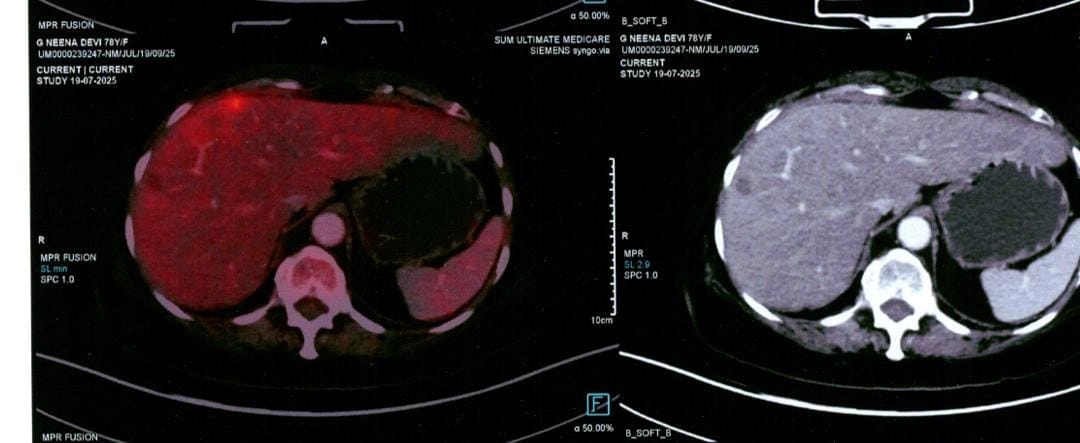

Considering her age and the presence of liver metastasis, a sigmoid colon resection with end colostomy was performed in April 2025. After discussion with the medical oncologist, it was planned to proceed with chemotherapy for the liver metastasis. She subsequently received four cycles of chemotherapy under close supervision, which were completed in July 2025. Follow-up PET-CT revealed regression in the size of the liver metastasis, with no new lesions, and no recurrence at the local site or in the peritoneum.